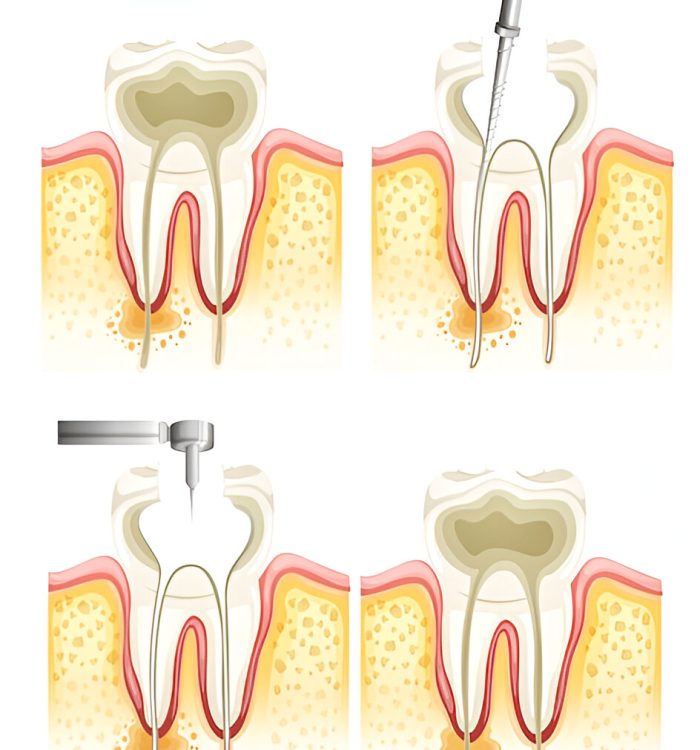

Deep Cleaning for Gum Disease

The performance of Scaling and Root planning functions to remove below-gumline plaque and tartar then makes root surfaces smooth for reducing regrowth.

Surgical Solutions

We perform flap surgery combined with bone grafting procedures to treat serious gum disease which helps maintain gum condition.